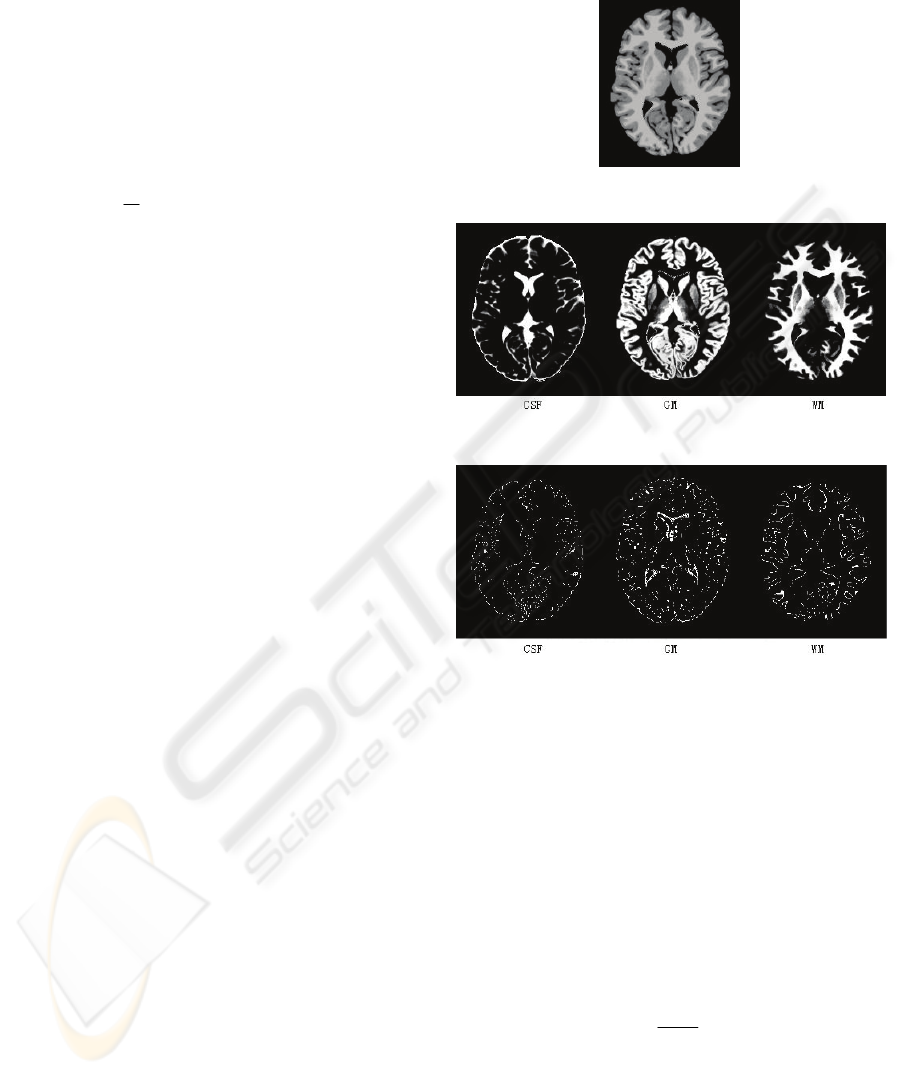

Results of real image Rn and Rt have been

compared to some manual segmenting results, and

they match each other. The improved method can be

well used for real applications.